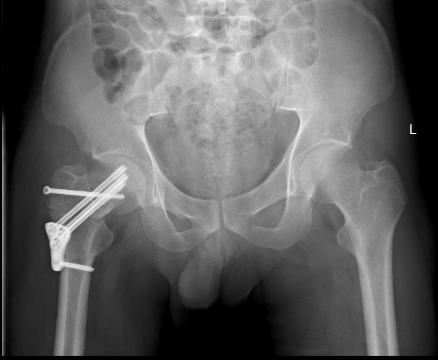

术后2周

3D打印在骨科应用并推广,因为骨科的专业特点与其技术特点吻合度颇高。借助3D打印,医生可以为患者“量身打造”钢板等内置物,有效解决了传统内置物与骨骼无法完全帖服和适形的难题,术前就可以对既有的钢板进行塑形使得内置物能够更好地发挥固定、支撑或替代作用,也大大地减少了手术时间,减少了手术的创伤,助力我院医疗质量的提升。

2015年12月,一名32岁的青年男性工作时不慎从高处坠落导致股骨颈骨折(经颈型)而入住我院骨创伤与手外科,考虑该类骨折具有很高的坏死率,患者越年轻坏死率越高。“以往,该类骨折手术的实施主要依靠患者的X光片进行手术分型,但X光片的缺陷主要在于其平面化,因此往往需要医生有一个立体空间的想象力,才能为接下来的手术做好铺垫。”即使行局部骨折三维重建也难以让手术医师有个直观的感觉,无法在体外对其进行术前预演。因患者体重较肥胖,骨折移位明显,为降低患者的股骨头坏死率的发生,科室主任陈跃平教授提出使用3D打印技术的“提前干预”,通过3D打印出他的全仿真患者股骨颈进行手术预演,因为有了预演的经验,最终手术得以精准、迅速完成,耗时较以往少了一半以上,目前创伤骨科已为近10位患者成功实施手术,患者术后恢复良好。